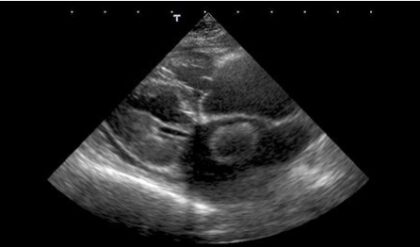

Die Echokardiographie stellt bei der Katze einen essentiellen Teil der Untersuchungsmöglichkeiten bei kardiologischen Problemen dar. Der Herzultraschall muss aber immer in Bezug zu den weiteren Untersuchungsmöglichkeiten gesehen werden, insbesondere bei Detektion sekundärer Kardiomyopathien. Gewisse Echokardiographische Grundmessungen wie die Größendimensionen und Wanddicken aus der rechtsparasternalen Längs- und Kurzachse, aber auch die Bestimmung der linksatrialen Dimensionen sind immer zu erhebende Daten. In diesem vetinar werden die einzelnen Messungen bei der Katze dargestellt und an Hand von Beispielen die verschiedenen Erkrankungen näher beleuchtet.